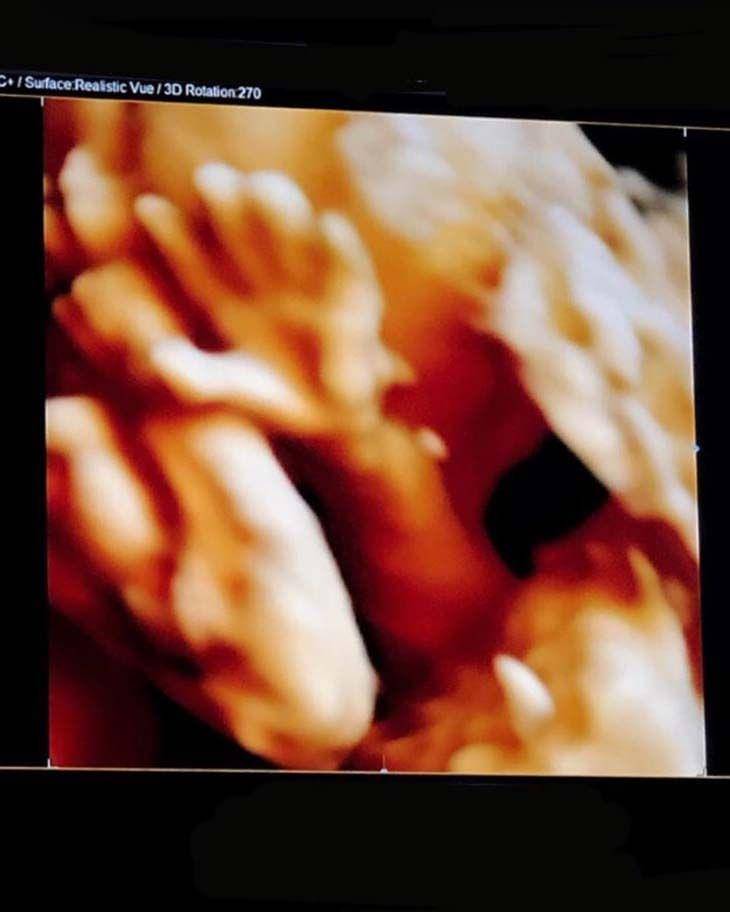

2. Berpandangan dengan si kecil melalui USG tiga dimensi

Berselang dua bulan setelah mengumumkan kehamilan sang istri, Edric kembali membagikan foto USG anaknya. Kali ini, Edric melakukan USG tiga dimensi yang memungkinkannya melihat wajah sang anak. Kegembiraan pun ia tunjukan dengan kembali bersyukur kepada Tuhan.